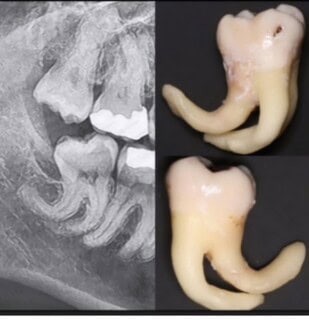

Hypercementosis

Hypercementosis…This is a great example of why some teeth are hard to extract! If the flare at the base is wider than the top - the extraction is complex!